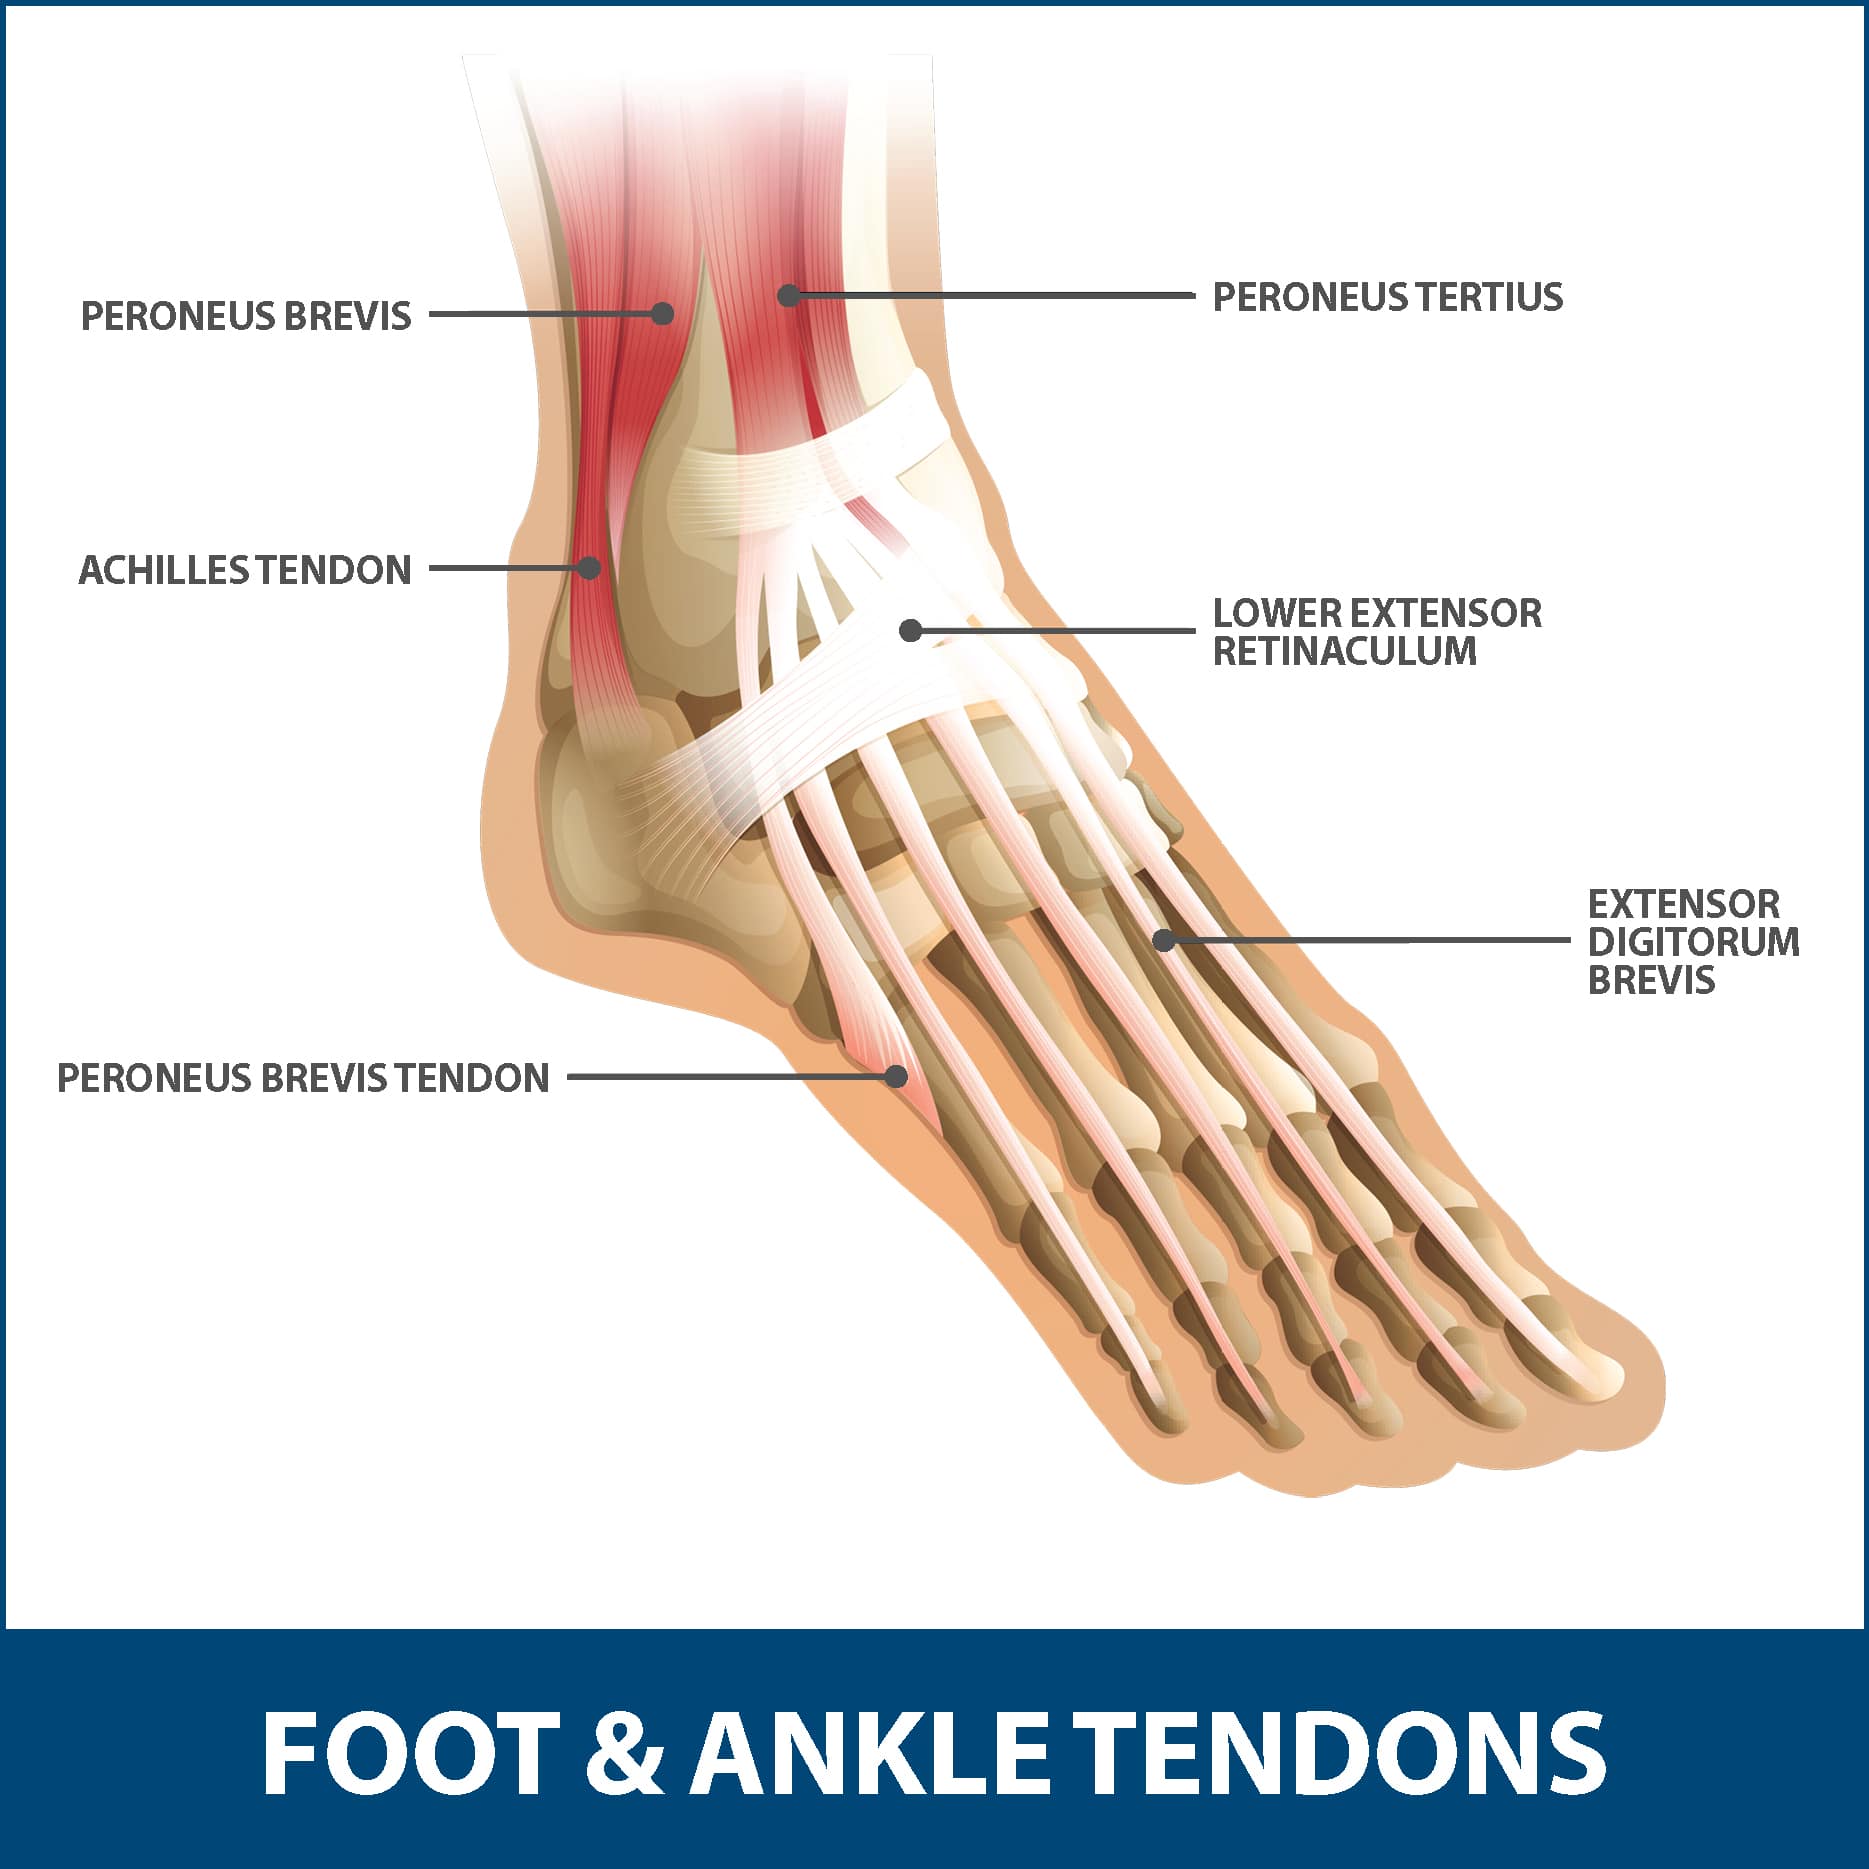

Achilles Tendon – NJSM

Achilles Tendon Diagram – 1000+ images about medical anatomy on …